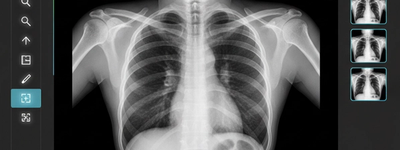

X-rays use a form of ionizing radiation to create images of the inside of your body. Ionizing radiation has enough energy to pass through tissues and produce detailed images of bones and certain organs.

When X-rays pass through your body:

- Dense materials like bone absorb more radiation and appear white.

- Softer tissues absorb less and appear darker.

- A detector captures the pattern to create the image.

A chest X-ray typically involves about 0.1 mSv, which is roughly equal to 10 days of natural background radiation.